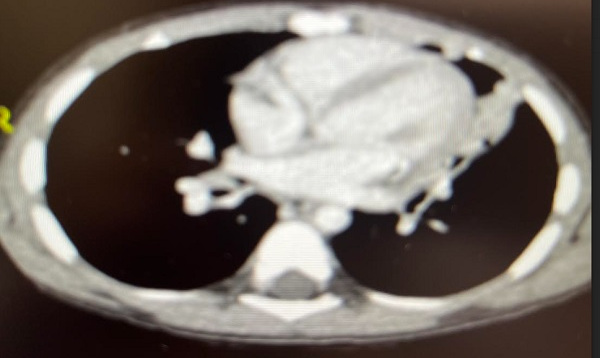

Dada la recurrencia de episodios, exploración alterada entre los mismos e imagen radiológica persistente, se realiza analítica sanguínea que incluye perfil inmunológico sin hallazgos y se remite a Respiratorio Infantil, donde se realiza tomografía axial computarizada (TAC): hallazgos sugestivos de proceso infeccioso broncoalveolar; atelectasia paracardiaca en língula (Figura 4).

Figura 4. Hallazgos sugestivos de proceso infeccioso broncoalveolar; atelectasia paracardiaca en língula